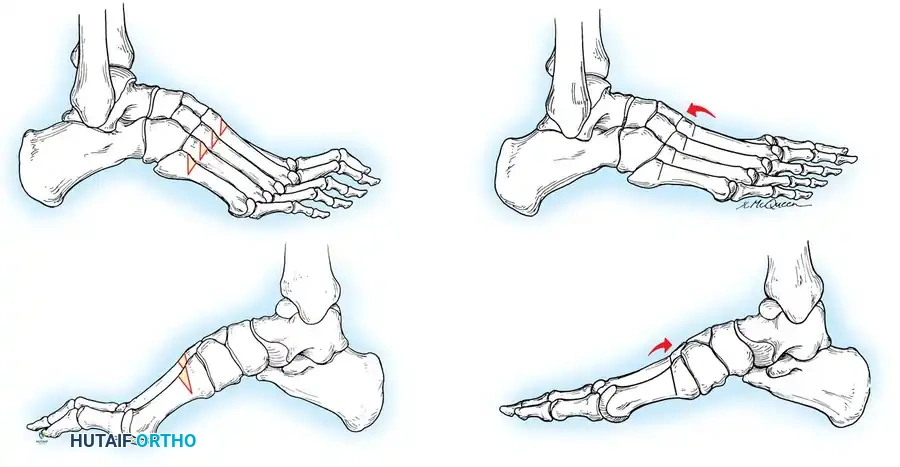

The flexibility of the anatomical components of the cavus foot dictates the surgical algorithm. The Coleman and Chesnut block test is the gold standard for determining the hindfoot-forefoot relationship and assessing whether the hindfoot varus is flexible or fixed.

Technique:

1. The patient stands with the heel and lateral border of the foot on a 1-inch wooden block.

2. The plantarflexed first metatarsal is allowed to hang free off the medial edge of the block.

3. If the hindfoot varus corrects to neutral or valgus, the hindfoot is flexible, and the deformity is entirely driven by the forefoot (the plantarflexed first ray).

4. If the hindfoot remains in varus, the deformity is fixed, necessitating a calcaneal osteotomy or hindfoot arthrodesis.

Fig. 6: Lateral block test. The plantar flexed first metatarsal hangs free; if the supple hindpart of the foot corrects, the varus is forefoot-driven.

Fig. 8: Planning the dorsal closing wedge osteotomy of the first metatarsal to correct forefoot equinus.